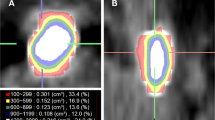

One hundred four patients treated consecutively with SWL for distal and proximal ureteral stones in our department between January 2010 and December 2013 were included in this retrospective study. Data analysis was conducted according to the declaration of Helsinki and approved by the Local Ethics Committee of St. Gallen (EKSG 15/055). Written informed consent for data analysis was obtained. NCCT was performed before treatment using a multidetector row helical CT scanner (Siemens, Definition Flash, Forchheim, Germany) with 30–460 mA, 120 kV and 2 mm collimation in every patient. As suggested in a study by Eisner et al. [9], stone size and Hounsfield Unit (HU) measurements were obtained in a standard bone window (window width-1,120 and window level-300). The image with the largest stone diameter was used to define maximum stone size. MAV was obtained by measuring the mean HU of defined regions of interest just smaller than the stone in magnified images without including adjacent soft tissue on each slice of the axial planes (Fig. 1). SSD was calculated as described by El Nahas et al. [3] and the distances at 0°, 45° and 90° were measured using radiographic calipers (Fig. 2). The average was calculated as the SSD. The measurements were performed analogous in prone position when targeting pelvic stones. The SSD was also measured and evaluated at an angle of 90° separately, as this seems to be the most important angle in the setting of the SLX-F2 (Storz Medical, Tägerwilen, Switzerland) which was used to perform SWL under sedoanalgesia.